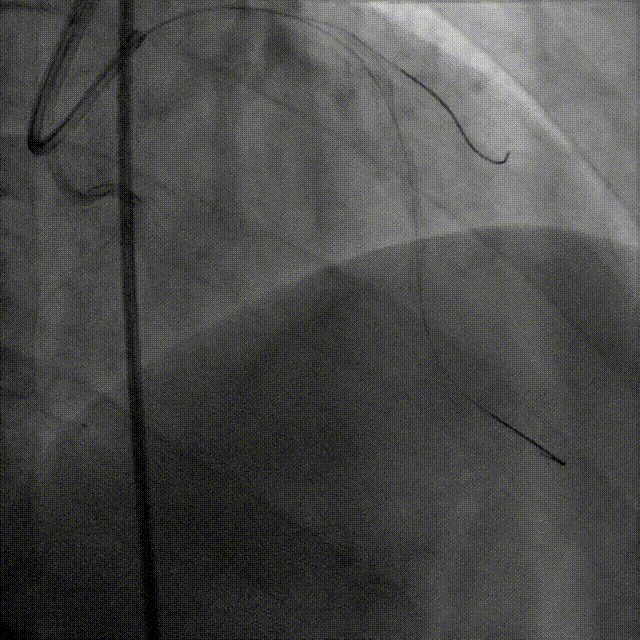

术后造影明确支架及心外膜侧枝情况

远端心外膜侧枝未见异常